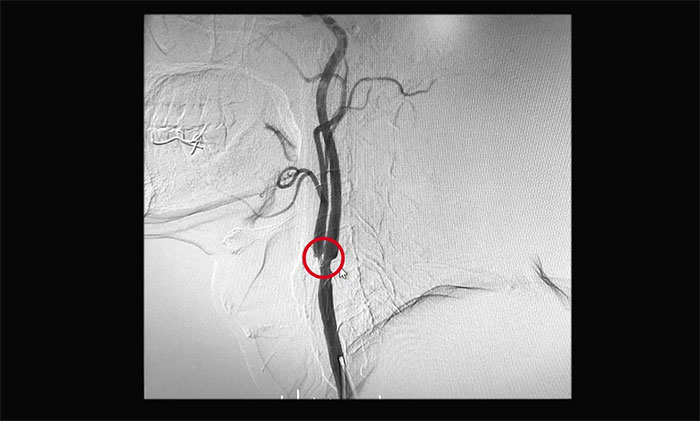

▲ 为患者开展DSA检查

医院神经外科6A病区医生团队详细了解黄先生的病史,并进一步完善相关检查。行DSA脑血管造影检查后,显示患者左侧颈内动脉起始部狭窄约70%,左侧颈外动脉起始部狭窄约90%,属于重度狭窄,应考虑手术治疗。

▲ DSA检查示左侧颈动脉重度狭窄